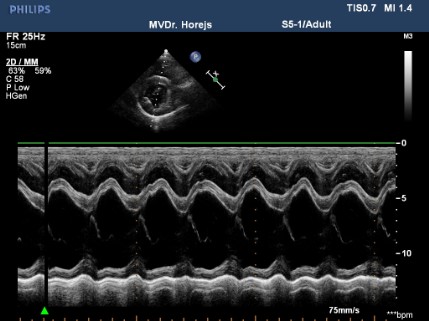

Myxomatózní degenerace mitrální chlopně